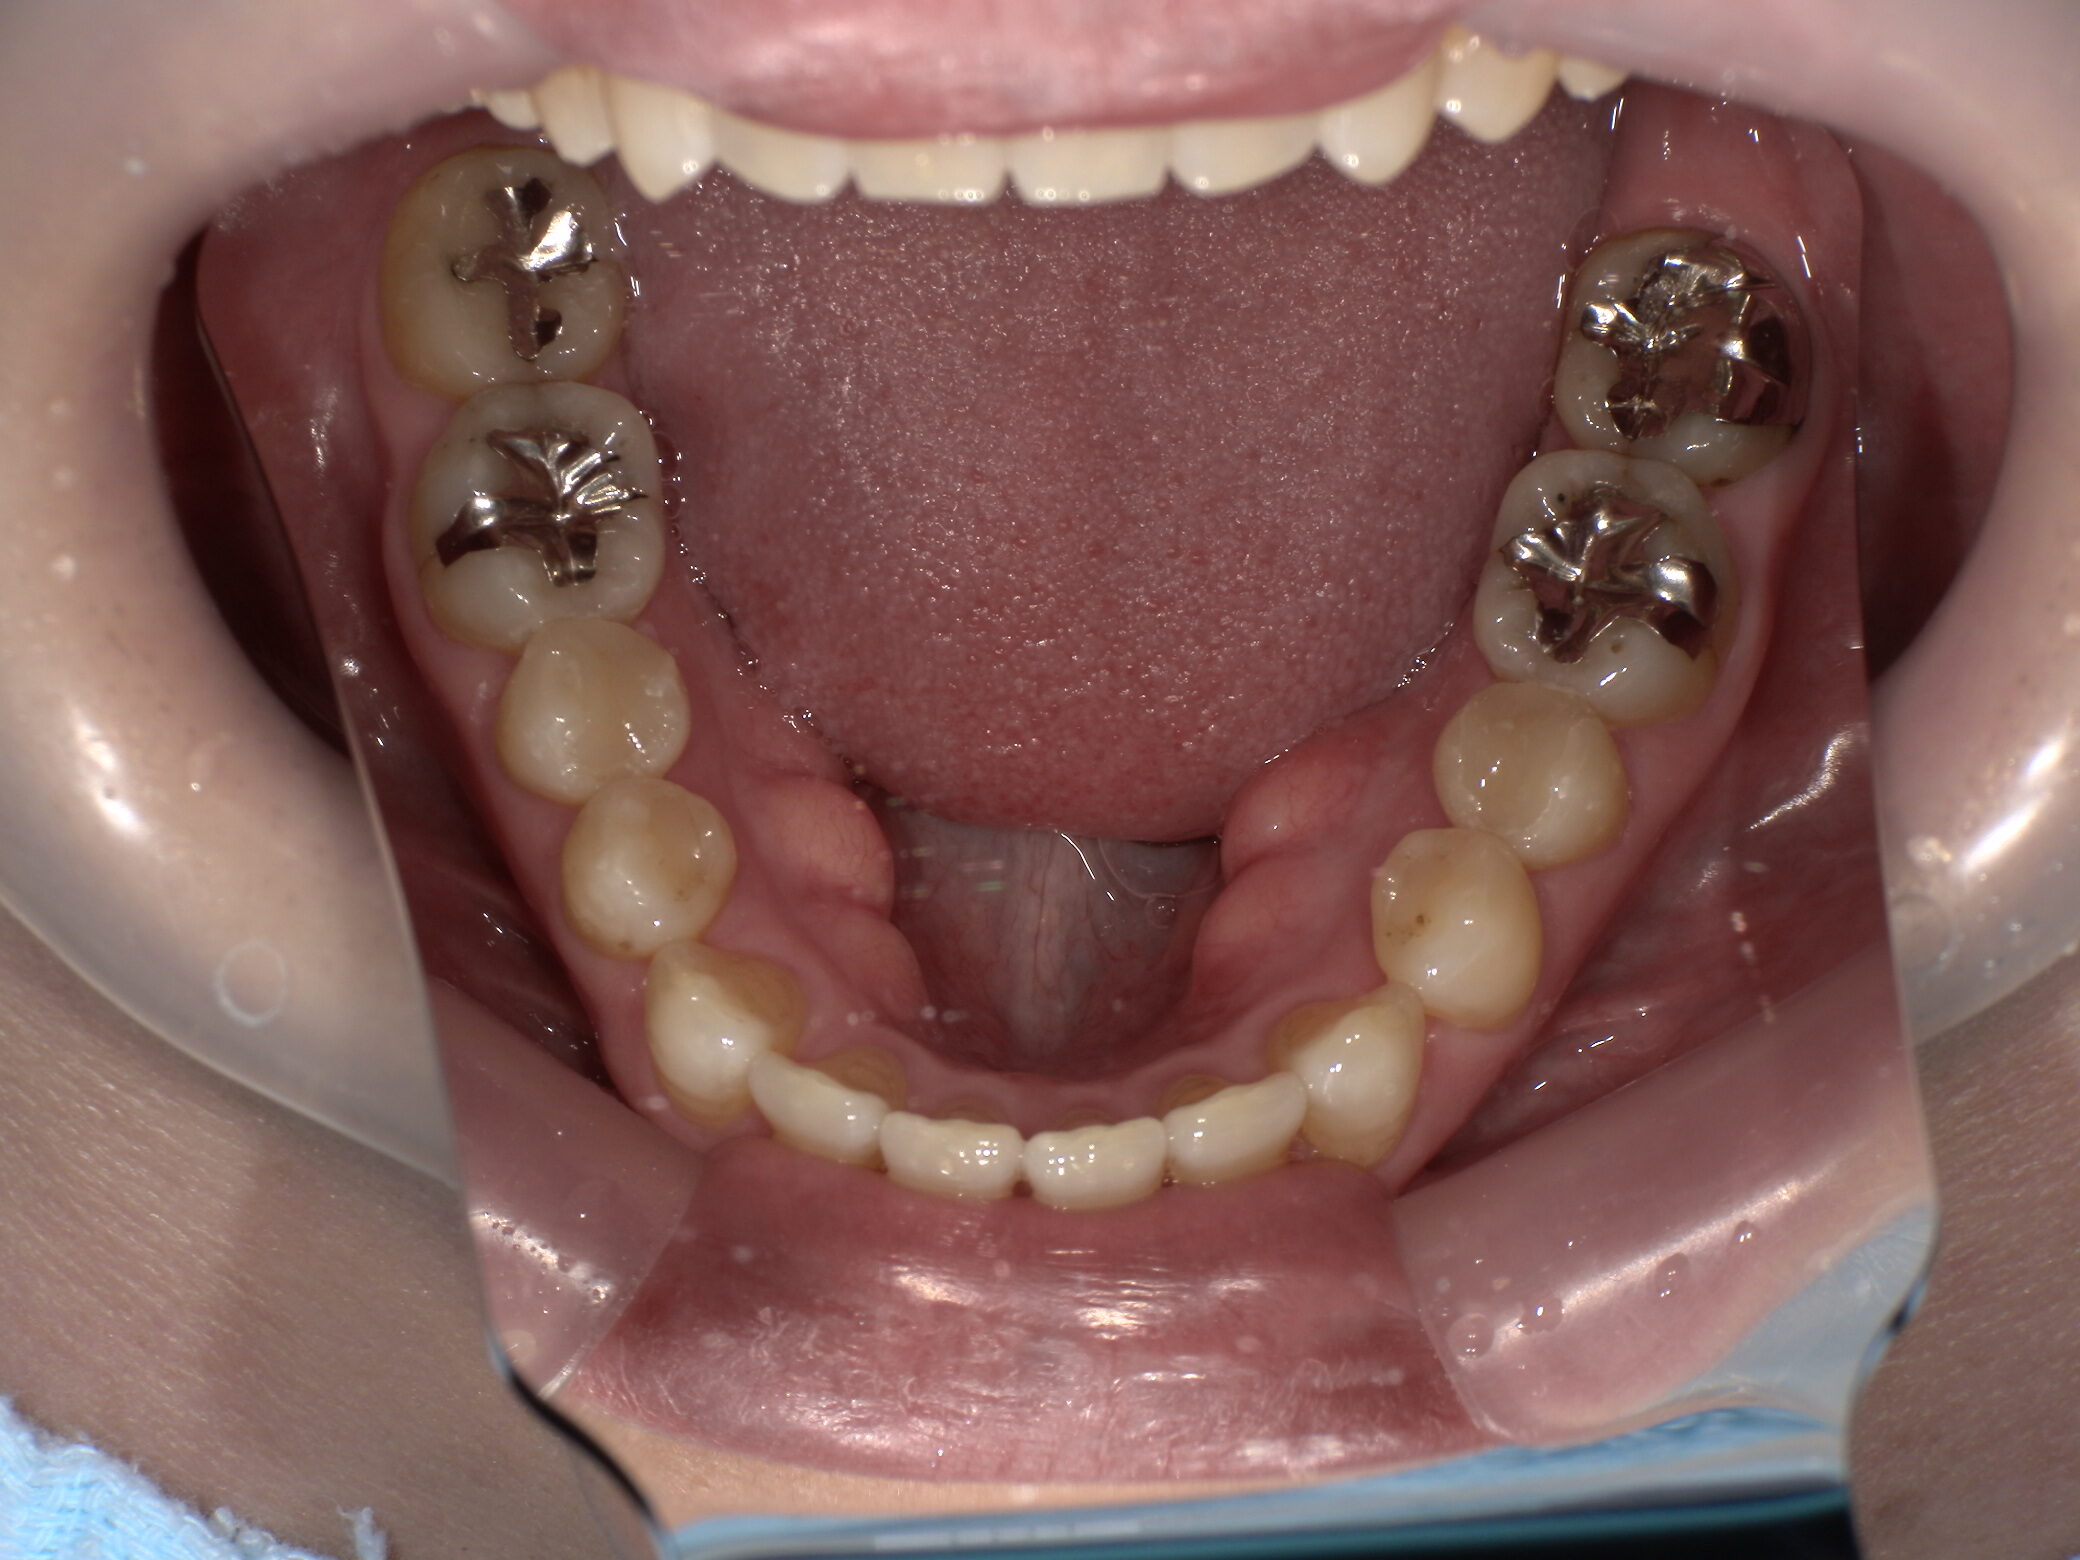

治療後 ![]() |

メタルインレーを除去し、う蝕を確実に除去した上で、メタルフリー修復としてセラミックインレーを選択。天然歯に近い色調・透明感を再現し、適合精度の高い修復を行いました。 |

金属色がなくなり、口を開けた際にも自然な見た目になりました。適合も良好で、清掃性が向上し、再発リスクの低減が期待されます。 |